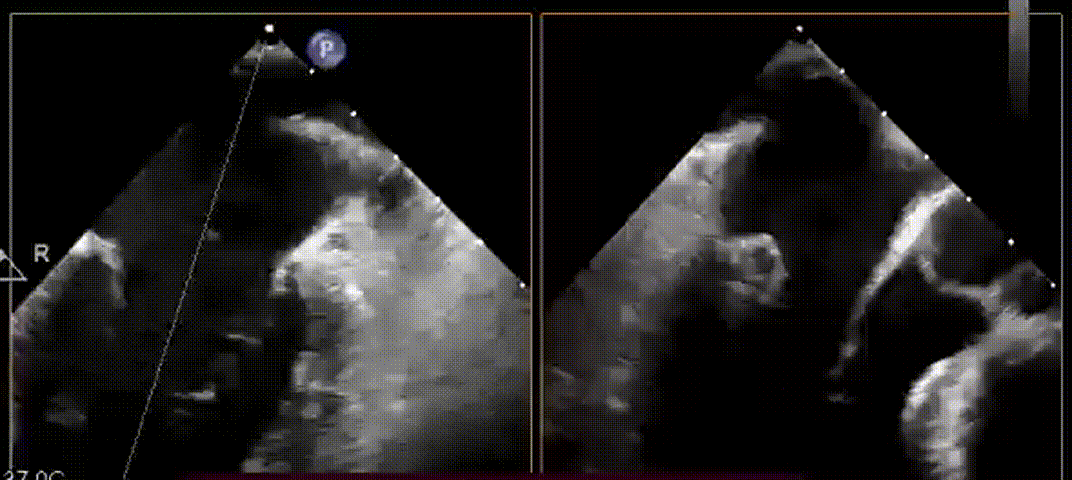

术中腱索植入、一键击发

患者全麻后,在左胸心尖对应处胸壁切开4cm微小切口,随即在经食道超声引导下,使用E-Chord®二尖瓣修复装置在P2-P3区域成功植入三对人工腱索并固定在心尖,二尖瓣反流立刻完全消失。手术全程约1小时,其中心内操作时间仅20分钟,可谓行云流水、一气呵成。手术无需体外循环、无需心脏停跳、无需心脏切开,E-Chord®系统直径只有 3mm(9F),是全球最细的二尖瓣修复装置,创伤极小,几乎无出血。手术在完全超声引导下进行,不但定位精确,且无任何放射线,堪称“绿色介入手术”。

E-Chord®二尖瓣修复装置的设计理念来源于外科手术,以极微创方式实现了二尖瓣的生理性修复。在本例手术中,E-Chord®装置超声显影清晰,操控灵活,指向明确,腱索植入点定位精准。瓣叶穿刺和腱索释放同步完成,快速简单,易于掌握。由于心脏不停跳,人工腱索可在超声引导下根据患者生理状态精确调整长度后固定。E-Chord®装置除了可实现腱索修复以外,配合迈迪顶峰已上市产品Easy-Knot®使用,理论上还可实现二尖瓣瓣叶“缘对缘”修复、三角形折叠以及对二/三尖瓣瓣环的“环缩”修复。